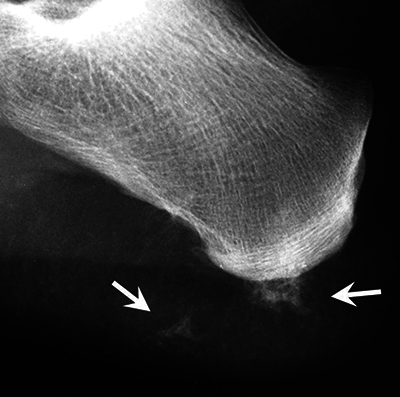

Teaching point: Some genetic syndromes have characteristic features that allow for their diagnosis to be made based on radiological findings.